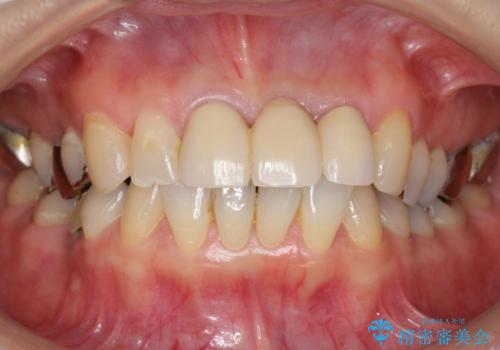

- 前歯のブリッジが不自然で気に入らないことを主訴に来院された患者様です。

前歯のレジン前装冠(保険内)によるブリッジは、金属で裏打ちされており透明感がなく不自然で、ポンティックも必要以上に長く作られていました。